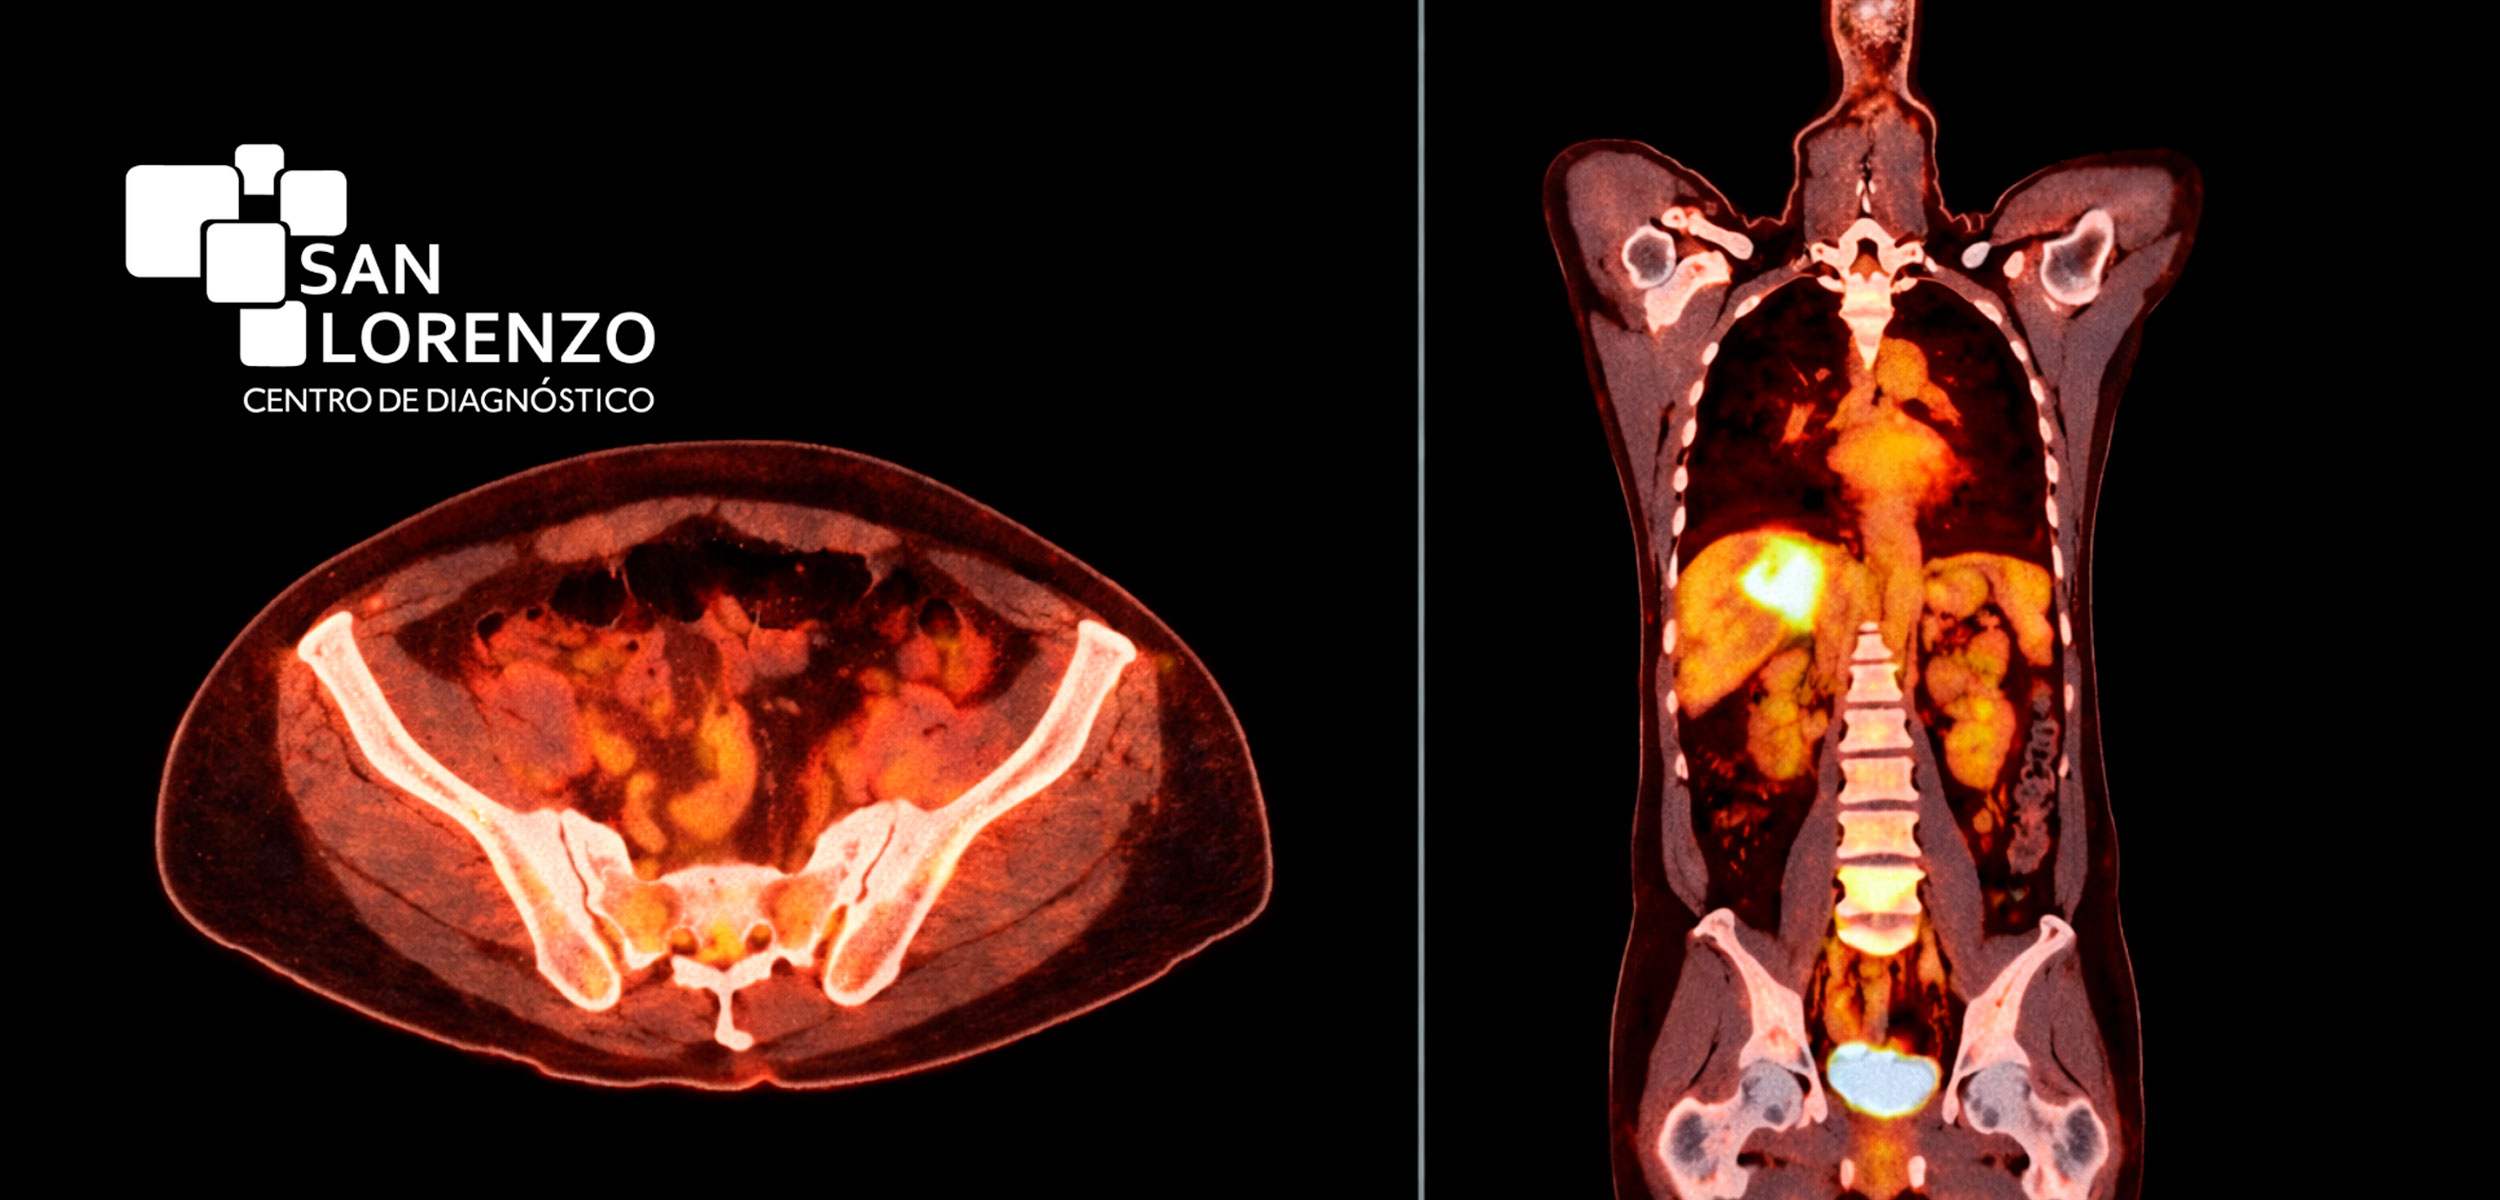

- PET/CT oncológico:: Para estudios oncológicos, tecnología híbrida que combina PET con CT o TAC, ampliamente utilizada por médicos especialistas para estudiar metástasis, controlar tumores, evaluar viabilidad cardíaca y detectar enfermedades neurológicas.